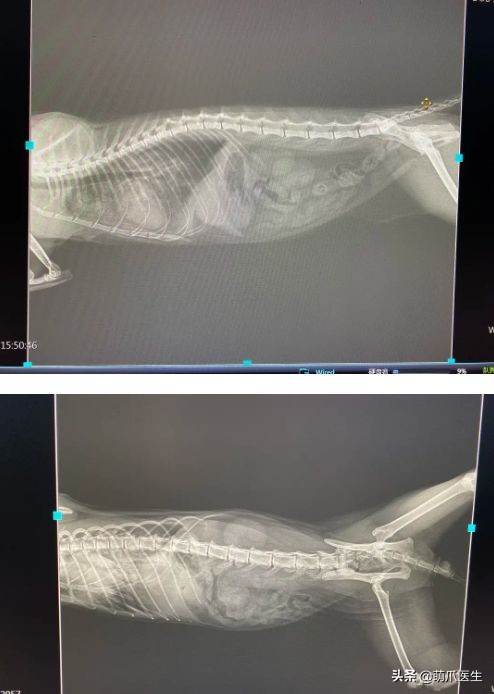

最后我们看一下X光片:

腹腔未见明显异常,而胸腔里肺部有一些渗出,心脏稍圆润偏大。

前面说到,十一的生化检查结果显示有心肌损伤的可能性,并且X光片发现肺部有水肿或者渗出。